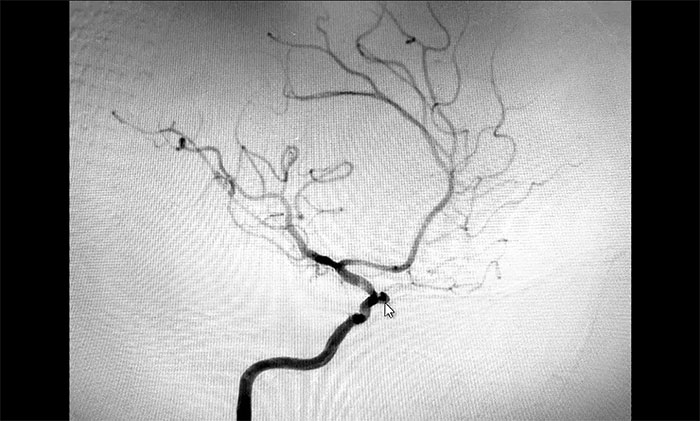

考慮腦出血后遺癥可能,于耀宇主任為秦女士完善相關(guān)檢查。通過DSA全腦血管造影檢查,發(fā)現(xiàn)患者右側(cè)頸內(nèi)動脈眼動脈段動脈瘤形成,瘤囊直徑約3mm,就像一顆長在動脈血管上的“葡萄”,里面充盈流淌著血液。

▲ DSA檢查發(fā)現(xiàn)顱內(nèi)動脈瘤

于主任介紹,眼動脈是眼眶及內(nèi)容物最主要的血液供應(yīng),是頸內(nèi)動脈主要分枝,也是交通顱內(nèi)外血管的重要通道。該處是頸內(nèi)動脈進(jìn)入顱骨后的第一個主要分支,如果患者血管壁先天發(fā)育缺陷或有高血壓等情況,在血流沖擊下,容易形成動脈瘤。